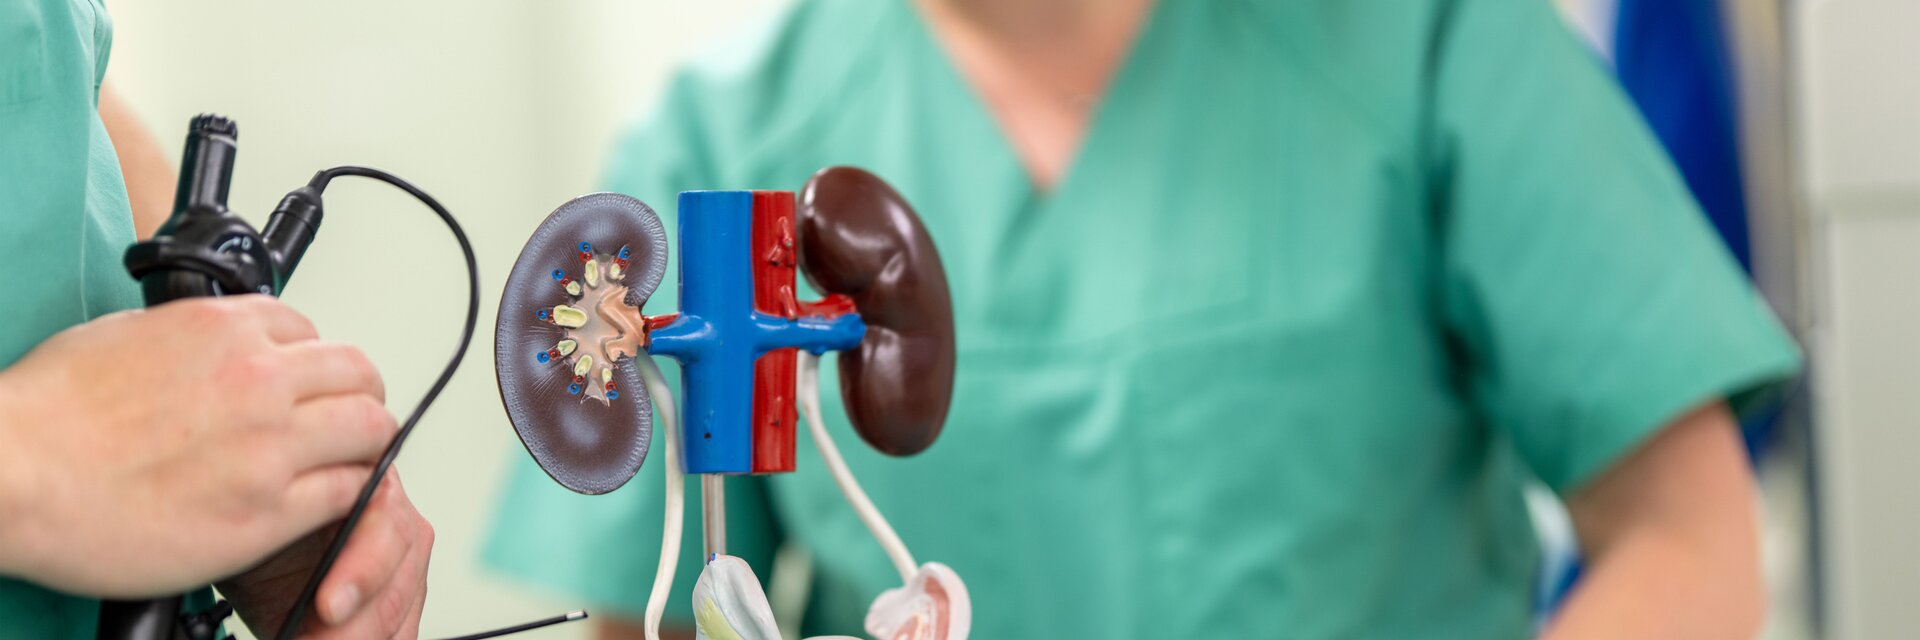

Als urologisches Steinzentrum arbeiten wir in der Klinik für Urologie und Kinderurologie nicht nur mit hochmodernen Therapieverfahren zur Steinentfernung, sondern auch mit den neuesten diagnostischen und therapeutischen Methoden und Geräten.

Mit minimal-invasiven Verfahren, wie beispielsweise der ureterorenoskopischen Steinentfernung, operieren wir möglichst schonend und gewährleisten zudem in der 24-stündigen Notfallversorgung schnelle Hilfe bei Nierenkoliken und anderen gefährlichen Akutzuständen.

Im urologischen Steinzentrum in Reifenstein behandeln wir Nierenkoliken, entfernen Harnblasensteine, Harnleitersteine und Nierensteine. Das Zentrum der Klinik für Urologie und Kinderurologie deckt das gesamte Spektrum der Steinentfernung ab.

Die ureterorenoskopische Steinentfernung ist eine besonders schonende Methode Steinleiden zu therapieren. Sie erfolgt minimal-invasiv. Bei der ureterorenoskopischen Steinentfernung führen wir ein Endoskop über die Harnblase in den Harnleiter ein. Nach Lokalisierung der Steine werden sie zertrümmert und entfernt. Mehr zu den Techniken, mit denen wir Harnblasensteine, Harnsteine oder Nierensteine entfernen, erfahren Sie nach dem Klick auf den untenstehenden Link.

Das urologische Steinzentrum im Eichsfeld Klinikum behandelt alle Arten von Steinleiden, von Nierensteinen über Harnleitersteine bis hin zu Harnblasensteinen. Dank der hochwertigen technischen Ausstattung und fortlaufender Weiterbildung unseres Personals können wir Steinbildungen frühzeitig diagnostizieren und in aller Regel medikamentös oder minimal-invasiv behandeln. Modernste Behandlungsverfahren wie die Steinzertrümmerung mit Hilfe von Lasergeräten stehen dabei sowohl bei der Abdeckung der 24-Stunden-Notfallversorgung für Nierenkoliken als auch bei geplanten Operationen zur Verfügung.